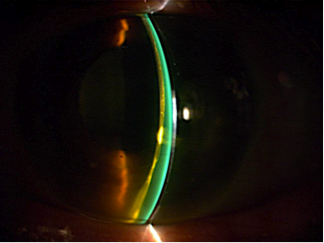

Abbildung 10: Messung der Überbrückung mit dem OCT

Die Abbildung zeigt die Überbrückung einer i-MATRIX Sklerallinse im optischen Schnitt(links) und im OCT dargestellt (rechts). Gemessen mit dem OCT, beträgt die Überbrückung der Kornea ca. 800 μm.

Die Abbildung 10 zeigt die Überbrückung der Kornea im optischen Schnitt (links) und die tatsächliche Überbrückung gemessen mit einem OCT (rechts). Die Überbrückung der zentralen Kornea beträgt ca. 800 μm. Anstatt die Änderung der zentralen Überbrückung von 450 μm zu schätzen, kann sie direkt berechnet werden. Für die Berechnung der Parameter der resultierenden Sklerallinse, stellen wir dem Anpasser ein Software-Tool zu Verfügung.